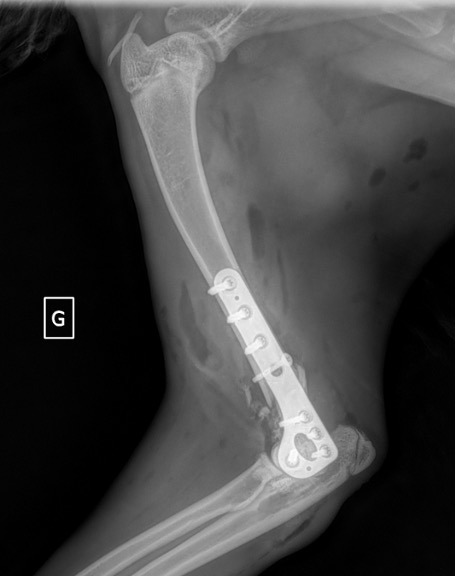

L’avènement récent des plaques anatomiques constitue une nouvelle option dans le traitement de ces fractures : dans l’exemple 3 (chat Ragdoll), une plaque anatomique médiale de 2 mm acceptant des vis de 1,6 et 2 mm a été utilisée seule avec succès.

Exemple 3 :

Figure 10 : Opération

Figure 11 : Post-Op Immédiat